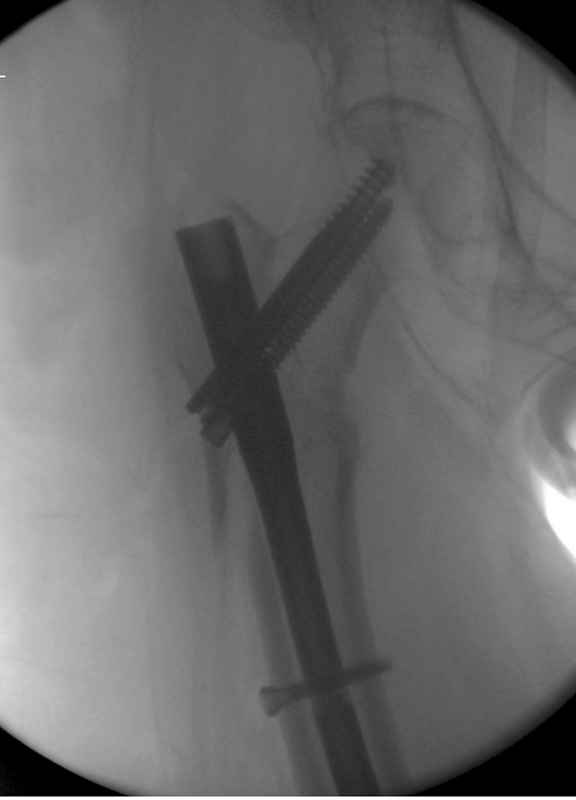

Здесь пара случаев фиксации похожих переломов:

первый высокоэнергетическая травма 36 лет

судя по картинкам с ЭОПа явно использовались приемы непрямой репозиции под его контролем, а так же интраоперационный ЭОП-контроль положения винтов, без такого контроля операция может ухудшить ситуацию (опять же учтите сроки) т.к. результат буде зависеть в большей степени от искусства хирурга, а не от технологии